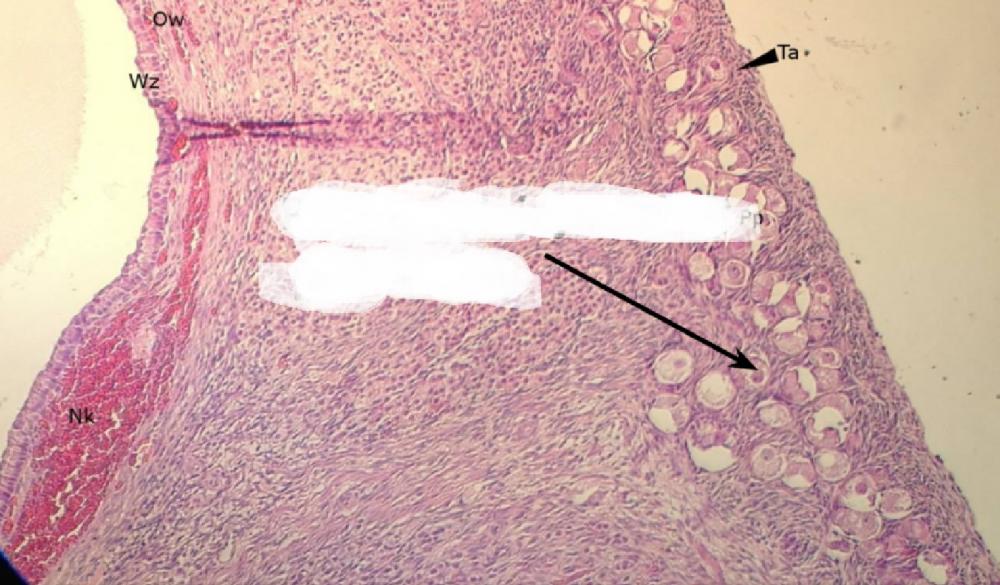

pęcherzyk atrezyjny (jajnik, kora)

błona biaława (jajnik, kora)

gruczoły śródmiąższowe (jajnik, kora)

warstwa ziarnista pęcherzyka (jajnik, kora)

osłonka wewnętrzna - obfita w komórki (jajnik, kora)

osłonka zewnętrzna - z dużą ilością włókien (jajnik, kora)